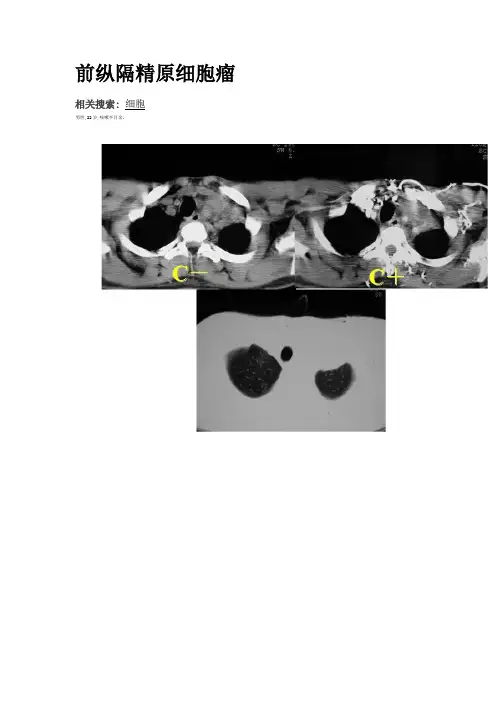

前纵隔精原细胞瘤

相关搜索:细胞

男性,22岁,咳嗽半月余。

结果:病理结果:(左锁骨上淋巴结)淋巴结转移性生殖细胞肿瘤,成分为精原细胞瘤。

精原细胞瘤与畸胎瘤一样,属生殖细胞类肿瘤,也是在胎儿或婴儿期形成,在年龄略大后才被发现,基本上发生于男性青年。

肿瘤细胞与睾丸的精原细胞类似,可以认为是纵隔的恶性生殖细胞瘤。

影像学表现无特征性,多位于前纵隔,呈分叶状,局限性生长或浸润性生长。

该肿瘤难与恶性畸胎瘤鉴别,但精原细胞瘤对放疗非常敏感,而且可依据其可能分泌绒毛膜促性腺激素(HCG),甲胎蛋白(AFP),以及乳酸脱氢酶(LDH)等,进行血清学检查以帮助诊断与鉴别诊断。